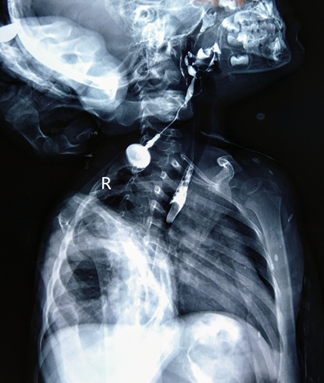

A contrast study was done by injecting iodinated contrast medium through the external opening, which revealed an irregular tract with beaded appearance on right side of neck extending cranially into the right lateral wall of oropharynx. Esophagus and stomach too showed the swallowed contrast, confirming the diagnosis of complete second arch branchial fistula.

Branchial apparatus consists of 5 mesodermal arches separated by invaginations of the ectoderm called as clefts. Anomalies of the branchial apparatus include branchial cysts, sinuses and fistulas.1,2 Branchial anomalies are common congenital lesions of the neck, of which second branchial complex anomalies are most common, accounting for about 95% of these lesions. A complete branchial fistula with 2 openings is rare.3 Branchial cysts are thought to occur due to entrapped remnants of branchial cleft or sinuses; branchial sinuses from entrapped remnants of cleft of pouches; and branchial fistulae occur from persistence of both pouch and cleft.4 The fistulous tract in second branchial fistula extends deep to the platysma, along the carotid sheath, and passes between carotid arteries bifurcation. Cranially, opening of the tract lies in the lateral wall of oropharynx at the region of tonsillar fossa.4 Second arch branchial fistula can be unilateral or bilateral. In case of unilateral, the right side preponderance is described.5 Fistulography and computed tomography (CT) fistulogram are the modality of choice for radiological diagnosis of second branchial arch fistula (Figure 1).1,3,5

Fistulography (performed with opacifying the fistula with contrast media) delineates the fistulous tract extending from the external cutaneous opening at the lateral neck to the tonsillar fossa.1,2 CT fistulogram with reformatted images demonstrates the fistulous tract as well as its relationship with important structures of the neck.1 Ultrasound and magnetic resonance imaging (MRI) has less diagnostic value in the diagnosis of fistulous tract, but more advantageous in the diagnosis of branchial arch cysts.1,5 Second arch branchial fistula are usually diagnosed in infancy or childhood with patient presenting with the complaints of watery or purulent discharge from an opening at the anterior aspect of lower third of the neck.3 The treatment of choice of second branchial arch fistula is complete surgical excision of the fistulous tract.1,2,4 Complete second arch branchial fistula is congenital anomaly of neck in the paediatric age group. The incidence of branchial fistula is less as compared to branchial cysts and sinuses. Fistulography (performed with opacifying the fistula with contrast media) is the best radiological diagnostic tool for pre-operative evaluation. Complete surgical excision is performed as the treatment of choice of second branchial arch fistula (Figure 2).